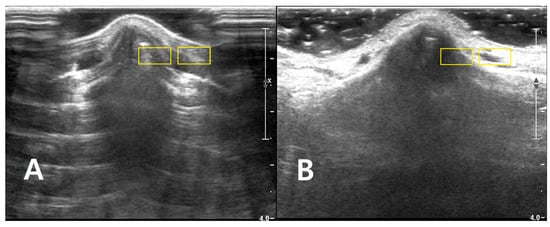

Two rectangular ROIs were defined at a fixed depth and orientation on the PAD image and then reapplied to the LGB image with only minor adjustments to maintain alignment: Cortical ROI (ROI_bone): A small rectangle (approximately 6 × 3 mm) confined to the bright cortical band at the nasal dorsum, avoiding saturated pixels (intensity = 255) and excluding overlying reverberation or shadowing. Adjacent soft-tissue ROI (ROI_soft): A rectangle of similar size placed 1–2 mm lateral to the cortical ROI at the same depth, sampling homogeneous soft tissue (Figure 2). The exact lateral position of the ROIs was adjusted so that, in both PAD and LGB images, ROI_bone and ROI_soft remained aligned to the same anatomical level (depth mismatch ≤ 0.5 mm; angular mismatch ≤ 5°). For subjects with cine data, the same ROIs were propagated across five consecutive frames: the frame with the highest mean intensity within ROI_bone and its two preceding and two subsequent frames. For each frame, the mean (μ) and standard deviation (σ) of the 8-bit gray-level values were recorded for ROI_bone and ROI_soft. For subjects with only static images available, ROI_bone and ROI_soft were repositioned across three to five adjacent locations along the same cortical segment, and measurements were averaged (Figure 3).

Figure 2. Longitudinal B-mode ultrasound images of the nasal dorsum in a volunteer illustrating ROI placement for quantitative analysis of each (A) PAD and (B) LGB image. Two rectangular ROIs (approximately 6 × 3 mm, yellow boxes) are drawn at the same depth. The image of cortical ROI was confined to the bright nasal cortical line, avoiding saturated pixels and obvious artifacts, and the adjacent soft-tissue ROI is positioned 1–2 mm lateral at the same depth to sample homogeneous soft tissue for CNR and SNR calculations. The images are provided for illustrative purposes to demonstrate ROI placement and were acquired.

Figure 3. Representative sonograms of isolated nasal bone fractures demonstrating ROI placement under two coupling conditions. For two different patients, longitudinal B-mode images of the nasal dorsum are shown with (A) PAD and (B) LGB. Two rectangular ROIs (approximately 6 × 3 mm; yellow boxes) were positioned at a matched depth in each image. One ROI was placed along the hyperechoic nasal cortical line, with care taken to avoid saturated pixels and obvious artifacts. A second, adjacent ROI was positioned 1–2 mm lateral at the same depth to sample homogeneous soft tissue. These examples illustrate the standardized ROI placement used across PAD and LGB images for subsequent CNR and SNR analyses. All images were acquired using the ultrasound presets described in Section 2.4 (depth, 4.0 cm; single focal zone at the nasal cortical interface). The images were cropped by 2.0 cm in the vertical direction to exclude the non-informative anechoic coupling medium visible on the screen; no additional rescaling was performed.